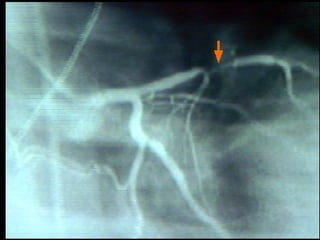

COMPLICACIONES HIPERTENSIVAS: Hipertrofia Ventricular Izquierda Disfunción Diastólica Disfunción Sistólica Insuficiencia Cardiaca Izquierda, Derecha Cardiopatía Isquémica

COMPLICACIONES ATEROSCLERÓTICAS: Cardiopatía Isquémica Enfermedad Vascular Cerebral Enfermedad Vascular Periférica

COMPLICACIONES HIPERTENSIVAS: HipertrofiaVentricular Izquierda Disfunción Diastólica Disfunción Sistólica Insuficiencia Cardiaca Izquierda, Derecha Cardiopatía Isquémica

COMPLICACIONES ATEROSCLERÓTICAS: CardiopatíaIsquémica Enfermedad Vascular Cerebral Enfermedad Vascular Periférica